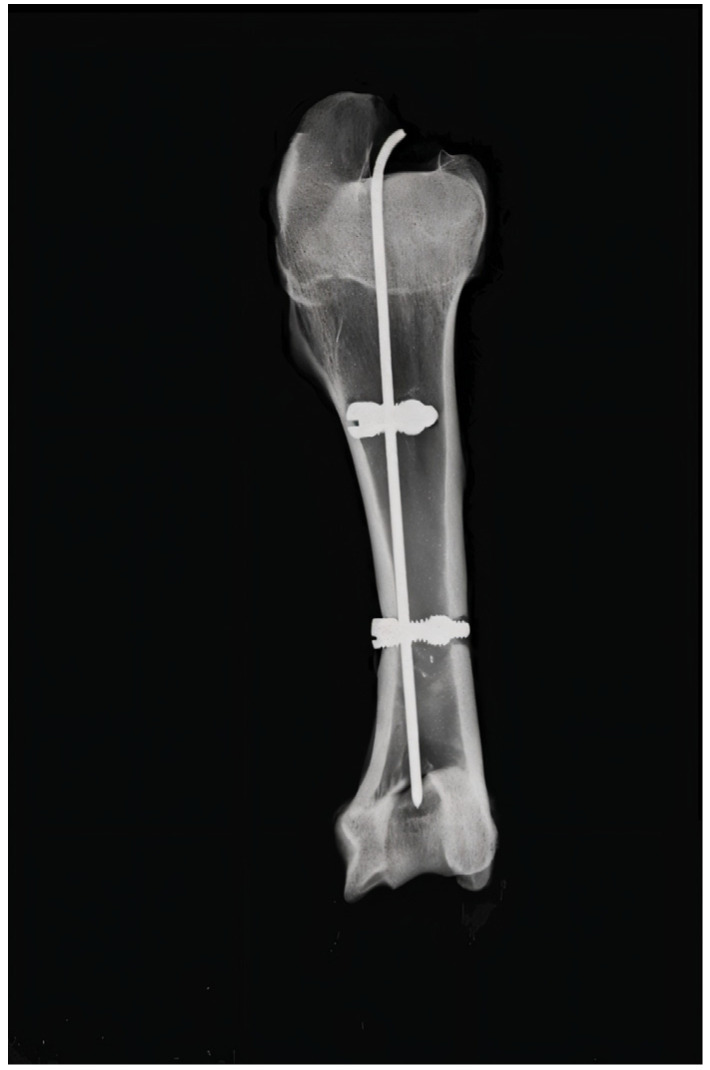

髓内钉广泛应用于长骨骨折。传统的系统是可靠的,但它们存在一些复杂性,如缺乏模块化或可能的生长板损坏。方法:开发并试验了一种新型的锁紧杆-螺钉系统,该系统具有中心杆和凹槽螺钉,具有二级联锁机构。机械测试遵循ASTM F543和ISO 6475标准,使用3.0毫米钢合金原型。结果:该系统在高达200 N的载荷下承受了20万次的机械测试,无失败率或松动率,明显优于其他相同尺寸的种植体(3.0 mm TENS)。结论:该种植体具有独特的空心螺钉和二次锁定结构,具有优异的体外生物力学性能。这种模块化的微创系统有望用于较小的长骨、个性化的儿科骨折和所有类型的骨干骨折,但仍需在体内验证。

Introduction: Intramedullary nailing is widely used for long bone fractures. Traditional systems are reliable, but they present some complications regarding lack of modularity or possible growth plate damage. Methods: A novel locking rod-screw system featuring a central rod and a grooved screw with a secondary interlocking mechanism was developed and tested. Mechanical testing followed ASTM F543 and ISO 6475 standards using a 3.0 mm steel alloy prototype. Results: The system withstood mechanical testing >200,000 cycles at loads up to 200 N with no rates of failure or loosening, significantly outperforming other implants of the same size (3.0 mm TENS). Conclusions: The proposed implant demonstrates superior biomechanical performance in vitro, enabled by its unique hollow screw and secondary locking configuration. This modular and minimally invasive system shows promise for use in cases of smaller long bones, personalized paediatric fractures, and all types of diaphyseal fractures, but does warrant in vivo validation.